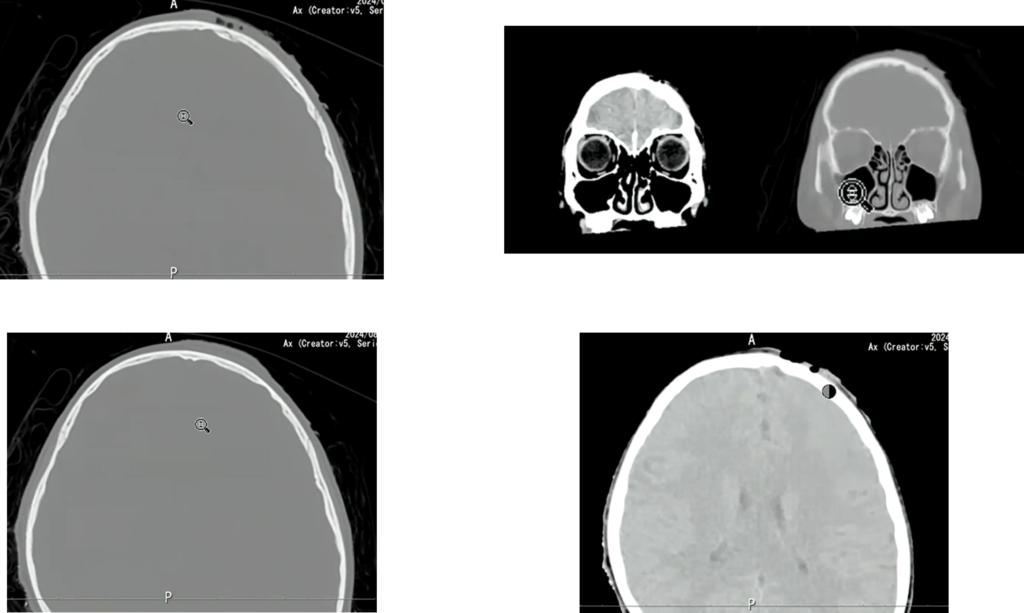

次に骨条件です。

受傷部には皮下気腫も伴っています。目立った出血や骨折はなさそうに見えます。

この時に最初のCT画像を振り返ると、実は”3D画像”がありました 。

画像がこちらです。

受傷部側の画像ですが、なにか気づきましたか?

受傷部の骨が一部陥没していることがわかります。

これを踏まえて、もう一度、骨条件の画像を確認しました。

一見すると異常が分かりにくい画像でも、3D画像を確認することで骨折の存在が明確になりました。

小児は骨が柔らかいため、外板のみが折れて陥没し、完全骨折に至らず所見が目立ちにくいことがあります。出血も初期は少量で、時間経過とともに明瞭化しました。本症例は外傷性陥没骨折、外傷性くも膜下出血・硬膜下血腫、脳挫傷と診断されました。